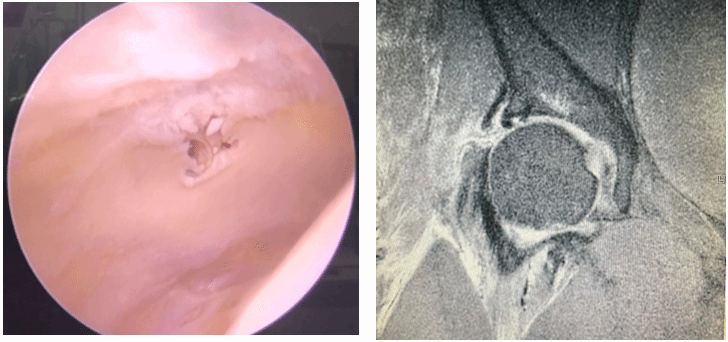

国际首创关节镜下软骨钉植入治疗髋臼软骨剥脱损伤,目前髋组已完成数十例髋关节镜下软骨剥脱修复术,在手术指征的选择,手术技术,围手术期管理等方面有较为先进的经验,处于国内领先,国际一流地位。

髋组进一步开展髋关节镜下盂唇重建手术,相关手术技术更加更熟完善,取得了良好的临床效果,并创新性的提出了微创膝关节外侧小切口取自体髂胫束的新型取腱方式,进一步提高取移植物的速度,减小取腱创伤,改进手术流程。